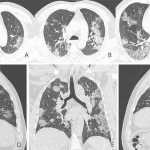

Σοκαριστικές αξονικές δείχνουν πώς ο κορονοϊός καταστρέφει τους πνεύμονες

Σοκαριστικές ακτινογραφίες ενός ανθρώπου που έχασε τη ζωή από κορονοϊό αποκαλύπτουν πώς η θανατηφόρα ασθένεια καταστρέφει τους πνεύμονες των θυμάτων της.

Ο Κινέζος ασθενής, ο...